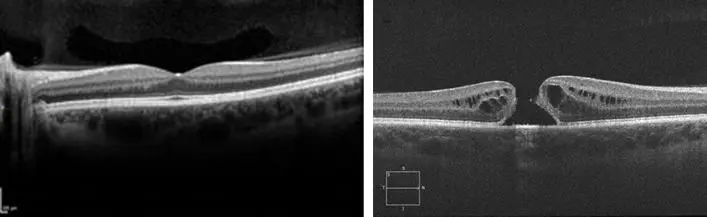

AGUJERO MACULAR

Se define como agujero macular a la pérdida de espesor completo del centro de la retina, zona que llamamos mácula, y se presenta de forma idiopática (influenciada por la edad, desprendimiento del vítreo que se contrae y tracciona el centro de la retina), y otras formas como traumática (un golpe fuerte), por miopia,entre otras.

Similar a la degeneración macular asociada a la edad, los síntomas que producen son en el centro de la visión (deformación al visualizar líneas, dificultad para enfocar el centro de las cosas).

El tratamiento actual es quirúrgico, mediante un procedimiento llamado vitrectomía. En esta cirugía se realiza un peeling de la capa más superficial de la retina y se coloca una burbuja de gas, la cual empujará la zona reparada y mejorará la probabilidad de que el agujero cierre.

Una vez que se desarrolla esta enfermedad, la posibilidad de curación espontánea sin tratamiento es muy poco frecuente, por este motivo, una vez diagnosticado, se le indicará cirugía para corregir la pérdida de tejido.

IMPORTANTE: AL IGUAL QUE EN MUCHAS ENFERMEDADES QUE OCURREN EN UN SOLO OJO, MUCHAS VECES LOS SÍNTOMAS PASAN DESAPERCIBIDOS A NO SER QUE UNO SE TAPE UN OJO Y VERIFIQUE LA DIFERENCIA ENTRE AMBOS OJOS, PORQUE CON LOS DOS OJOS ABIERTOS MUCHAS VECES NO NOTAMOS LA DIFERENCIA

Izquierda: Mácula Normal | Derecha: Agujero Macular